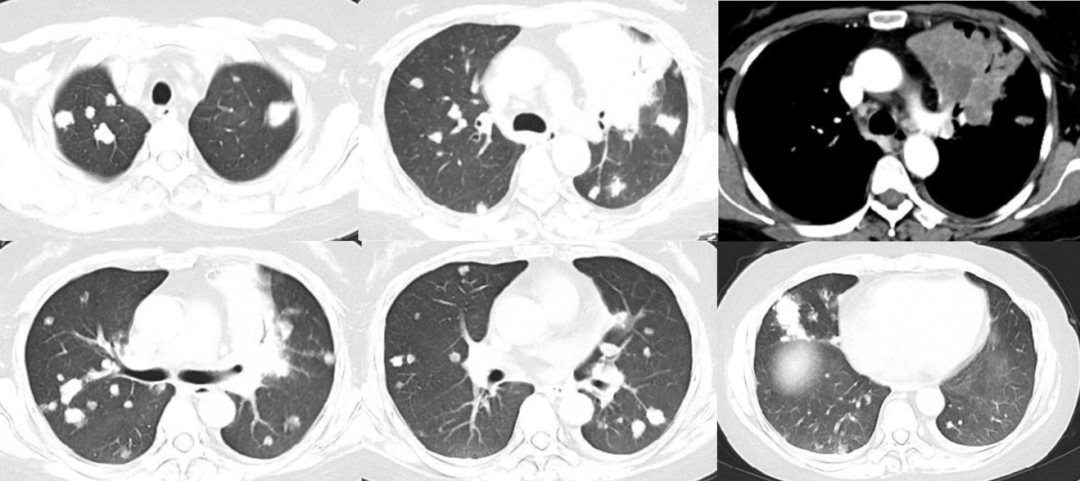

一位19岁女性,有缺铁性贫血史。间断腹痛半年,近3月消瘦10kg,上腹痛伴发热盗汗、干咳1周。胸片及肺CT可见双肺弥漫小结节影,部分融合倾向。3次诱导痰均抗酸菌阳性。[7]

影像中可见斑片结节状的病变相对均匀地弥漫分布于双肺。如果说是沿着气道,又没有明显的树芽症表现,如果说是血行播散,这些病变比一般的粟粒性肺结核又显然粗大的多。所以这个影像是非常特别,有些像转移瘤。但仔细看这些斑片结节几乎都不与胸膜接触,同时其边缘并不清晰光滑而是呈开花状,提示它的本质很可能是小叶中心性结节。

下面这是我们自己最近遇到的一个病例:

44岁的中年女性,既往健康,无症状,因新冠筛查而发现肺部阴影。肺部CT主要为双肺多发结节团块影,增强扫描纵隔窗显示左上肺前段的大片实变内有多发低密度影。当时大家讨论持各种意见的都有,包括转移瘤、真菌、结核或其他分枝杆菌,还有奴卡菌等等。

面对如此不典型的影像,只能继续往前工作。很快做了支气管镜,左上肺灌洗及肺活检均找到抗酸菌,灌洗液分枝杆菌培养Mtb(+)。所以有一句老调重提的话,临床上千万不要轻易排除结核,它可以模拟各种疾病。但是另一方面,深入理解结核病的病理机制,有助于认识一些反常临床表现的本质,而通过有目的地阅读肺部CT,仍可能在一些不典型的病例中发现提示结核的蛛丝马迹,为诊断提供线索。